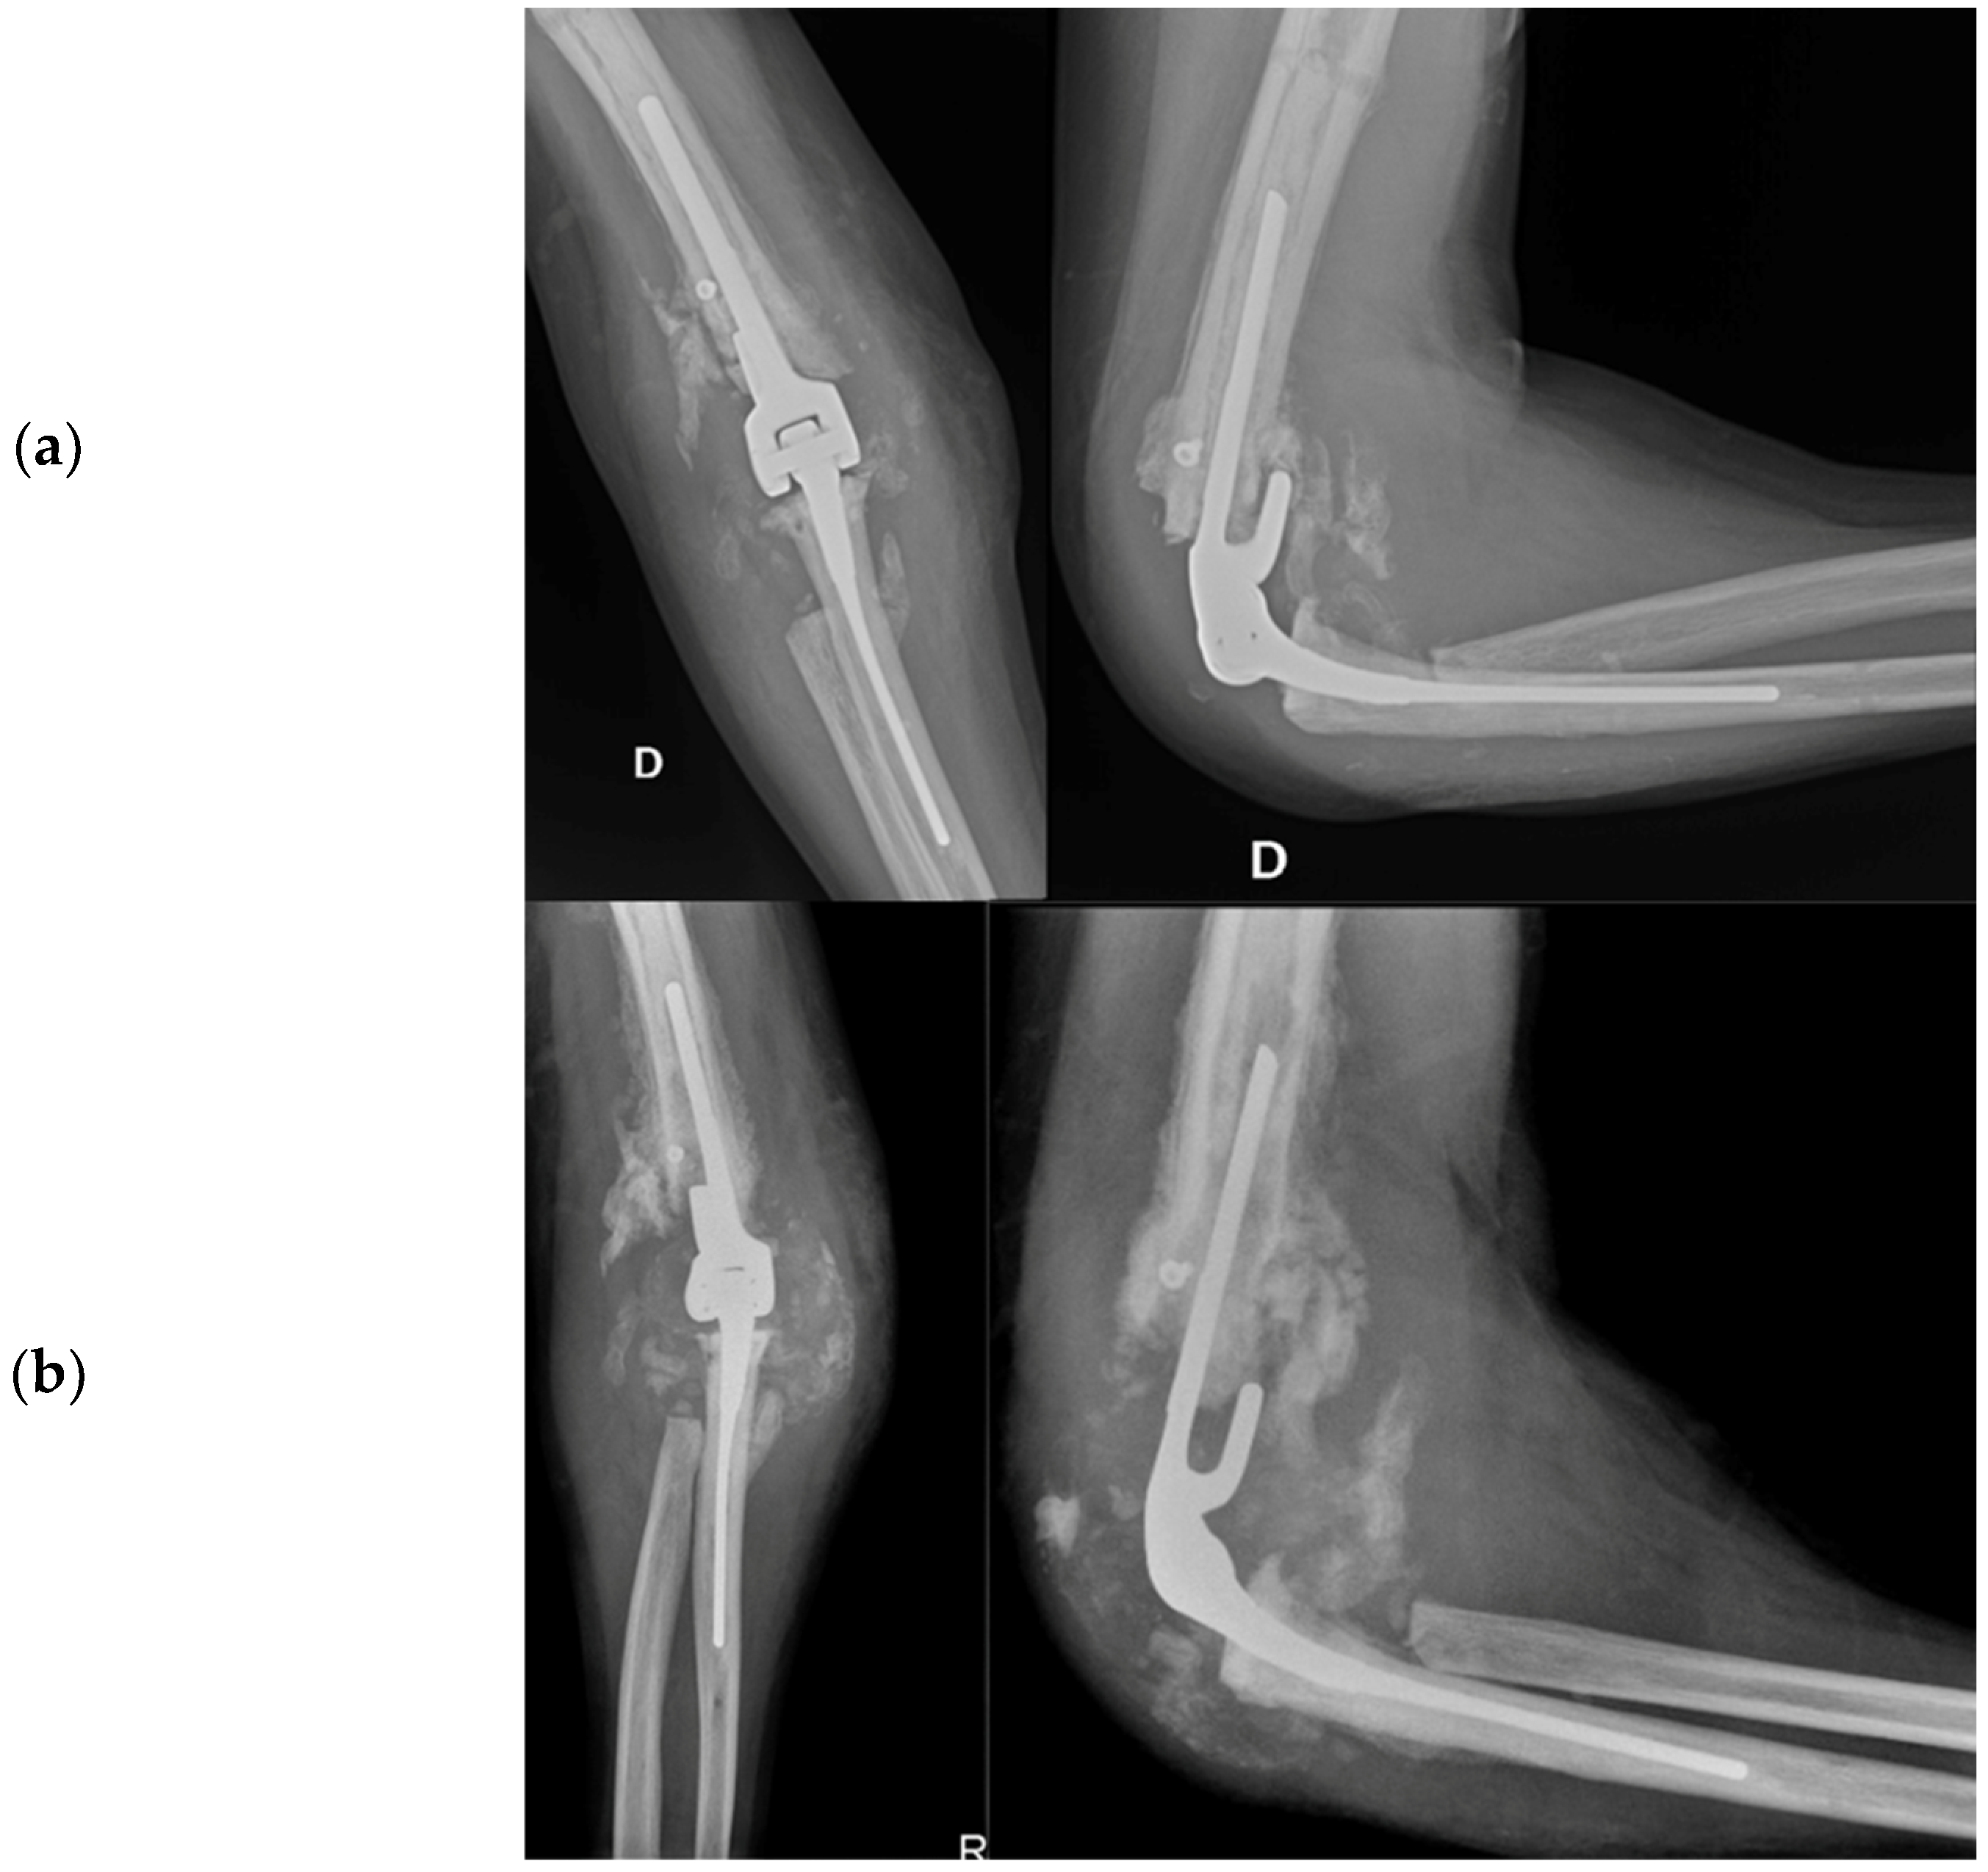

The patient utilized the external fixator for a period of two months in order to facilitate the healing of their soft tissue. Following this period, the patient underwent TEA surgery in November of 2013. During the procedure, the broken screws were removed and the distal epiphysis of the humerus and ulna were prepared for the implantation of a Coonrad–Morrey prosthesis with a humeral stem extra small/L 100 mm cemented. The extensor apparatus of the ulna was stabilized with a non-resorbable fiber wire, and post-operative X-rays revealed the proper placement of the prosthesis (shown in Figure 8). The patient was instructed to maintain a 90-degree cast on their elbow until the wound had healed, followed by careful mobilization. Tranexamic acid was prescribed for a week, and the wound-healing process was successful, with the patient achieving a range of motion in flexion of approximately 100 degrees fifteen days after the TEA surgery.

Figure 8.

X-ray anteroposterior and lateral views of the right elbow after the placement of the total elbow arthroplasty (TEA) with the restoration of normal joint relationships.

Two months post-TEA surgery in February 2014, the patient faced complications despite satisfactory elbow flexion (approximately 120°). Calcific deposits increased, and a faint radiolucent line appeared around the prosthetic humeral stem, with no changes to the ulnar stem. A radiograph taken 15 days later showed humeral TEA loosening, increased radiolucency at the apex and along the stem, caudal dislocation, and resorbed calcific deposits as shown in Figure 9a. The patient was also hospitalized for Hodgkin’s lymphoma recurrence, presenting with local swelling and elevated inflammatory markers: ESR at 41, CRP at 7.68 mg/dL, and WBC at 10.06 thousand/mm3.

Figure 9.

(a) Radiographic X-ray anteroposterior and lateral views: beginning of prosthesis loosening with increased bone radiolucency around the prosthesis; (b) 30 days after loosening of the prosthesis and increasing of periarticular calcifications.

A subsequent CT scan confirmed humeral stem loosening, caudal displacement, and mediolateral tilting. Significant bone loss around the prosthesis was evident, with lytic bone remodeling and periosteal reaction. The ulnar portion was well fixed but showed periosteal reaction. Intra-articular loose bodies, capsular calcifications, and soft tissue swelling were also observed. The radiologist suspected advanced HA but could not exclude arthritic synovitis of infectious origin or lymphoproliferative disease.

After the patient’s elbow became swollen and hot with limited ROM and an audible click, an open elbow cast was applied, a blood culture was taken, and empiric antibiotic therapy with Trimethoprim/sulfamethoxazole (160 mg/800 mg) and Minocycline (100 mg) was initiated. However, a follow-up radiograph after 15 days showed an increase in joint calcifications and no improvement in implant loosening, as shown in Figure 9b.